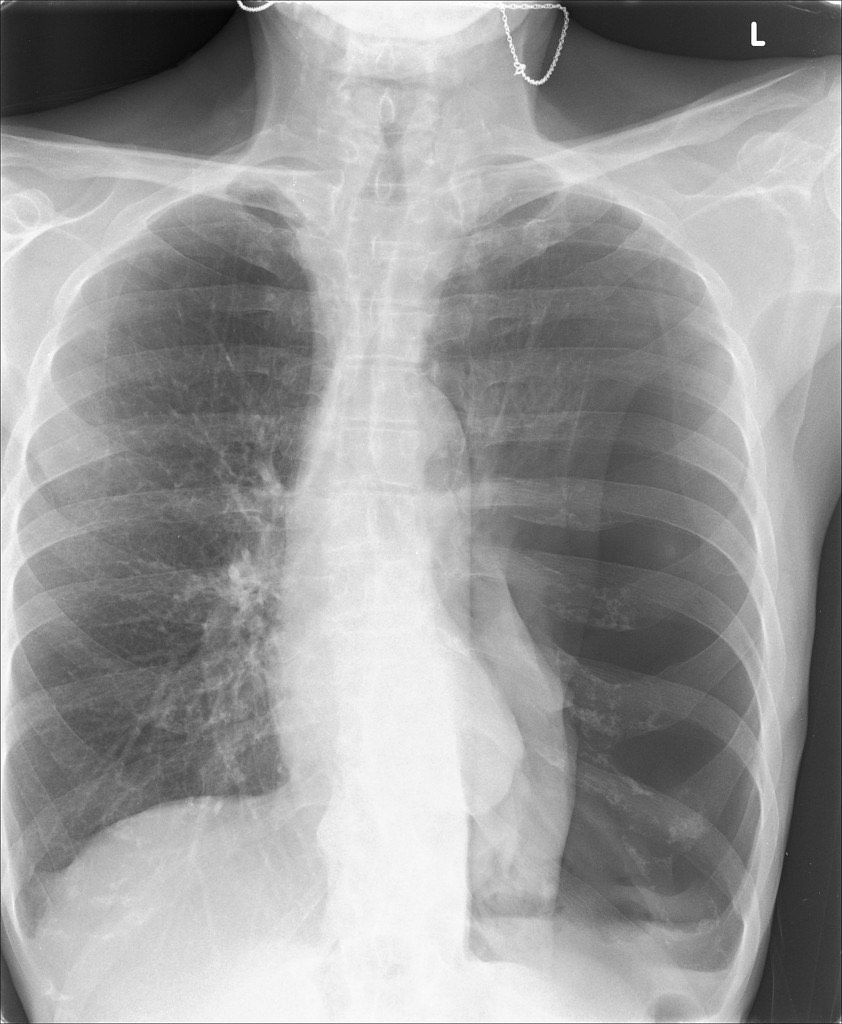

2819. У пациента с жалобами на одышку в покое на протяжении двух дней повышение температуры тела до 37,1°С, сердцебиение и гипотензия, рентгенологические данные, представленные на снимке, наиболее вероятно, соответствуют клинической картине